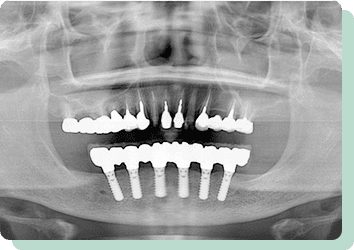

上の歯は残っており、下の歯は全て抜けてしまったケースです。総入れ歯にした場合、受圧加圧のバランスが悪く、何でも噛める入れ歯を作ることは困難です。歯があった時のように食べれるようにという希望でしたが、十分な満足を得ることが出来ました。術後10年以上経過しましたが、問題なく機能しています。

リスク:疼痛・咬合時痛・冷水痛・出血・インプラント手術による歯ぐきなどの損傷・インプラント周囲炎など

費用:インプラントケース総額 2,640,000円